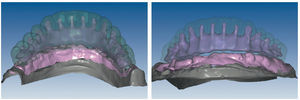

Mediante el uso de un escáner óptico de luz estructurada, los protocolos CAD registran los primeros datos relativos al modelo maestro con las correspondientes posiciones de implante (figs. 87 y 92). En el siguiente paso tiene lugar la digitalización de la planificación, previamente realizada en cera de escaneo matificada, de la restauración definitiva (figs. 88, 90 y 93). La subsiguiente conciliación de los datos mediante el uso del software de diseño dental permite al protésico planificar virtualmente el resto del procedimiento (figs. 89 y 91, 94 a 96) a partir del diseño de las estructuras (figs. 97 y 98).

Fig. 87. Imagen CAD del modelo maestro superior.

Fig. 88. Imagen CAD de la planificación definitiva para el maxilar superior.

Fig. 89. Planificación CAD de la estructura del maxilar superior.

Fig. 90. La posición de los implantes en relación con la planificación.

Fig. 91. El diseño definitivo de la estructura para el maxilar superior.

Fig. 92. Imagen CAD del modelo maestro del maxilar inferior.

Fig. 93. Imagen CAD de la planificación definitiva para el maxilar inferior.

Figs. 94 a 95. Planificación CAD de la estructura del maxilar inferior, en representación lingual y vestibular.

Figs. 96 a 98. El diseño definitivo de la estructura del maxilar inferior, desde distintas perspectivas.